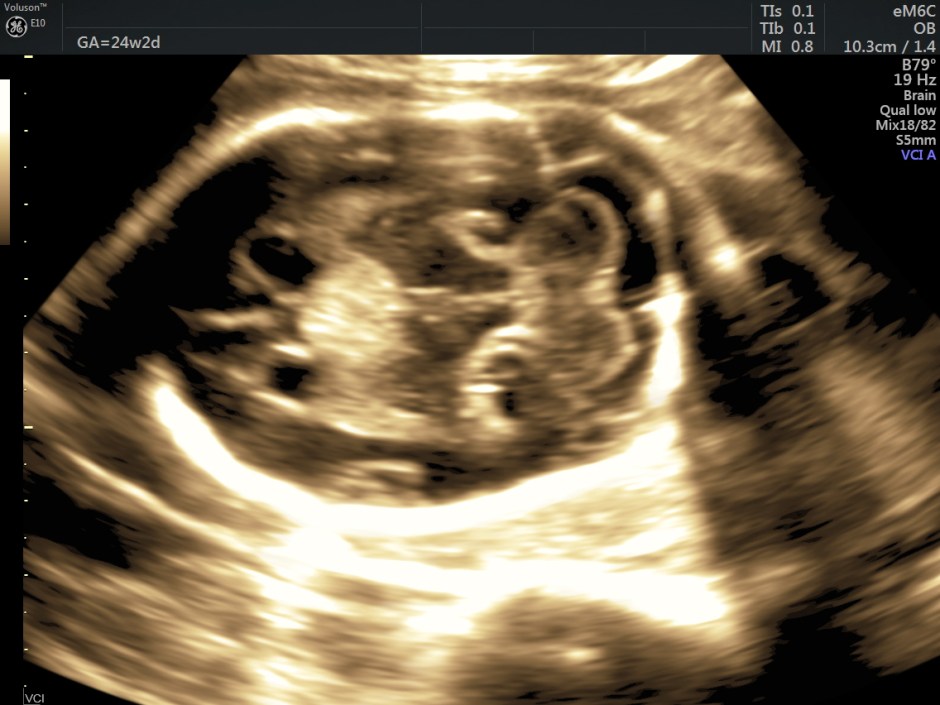

Some reconstructed images are given below.

The sonographic and MRI appearance of the intracranial teratoma is usually that of an irregular solid mass, in some cases with cystic and/or calcified components, distorting brain anatomy.

In this patient, reconstructed images show the corpus callosum to be formed.